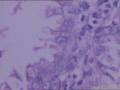

性别年龄50临床诊断

一般病史流血3月

标本名称宫内刮出物。

大体所见灰白色碎组织多枚:1.2x1x0.6CM

请把性别改过来吧!高度分泌子宫内膜,有A-S反应,请做HCG检测

子宫内膜高度分泌反应,间质蜕膜样变

高度分泌子宫内膜,有A-S反应,间质蜕膜样变,请做HCG检测.

子宫内膜高度分泌反应伴间质蜕膜样变。

高度分泌子宫内膜,有A-S反应,间质蜕膜样变.

50岁,所以有所怀疑,后经主治医生做HCG水平低,她忧忧的道出:可能是前一年轻病人流产清宫后,负压瓶未处理干净所致。